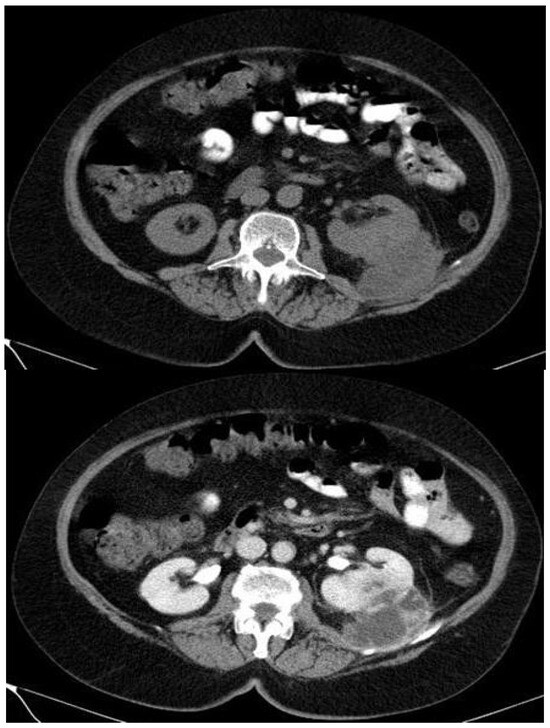

- CT is considered the imaging technique of choice in the diagnosis of the disease preoperatively and a plethora of CT characteristics have been described so far.